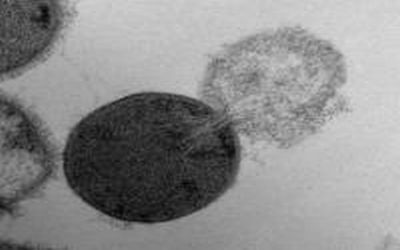

This is a transmission electron microscopy image of a Streptococcus pyogenes cell experiencing lysis after exposure to the highly active enzyme PlyC.

The balance between the bending and pressure forces led to the model prediction that holes 15 to 24 nanometers in diameter or larger would cause a bacteria cell to burst. To test the theory, Daniel Nelson, an assistant professor at the University of Maryland, used transmission electron microscopy images to measure the size of holes created in lysed Streptococcus pyogenes bacteria cells following PlyC exposure.

Nelson found holes in the lysed bacteria cells that ranged in diameter from 22 to 180 nanometers, with a mean diameter of 68 nanometers. These experimental measurements agreed with the researchers' theoretical prediction of critical hole sizes that cause bacterial cell death.